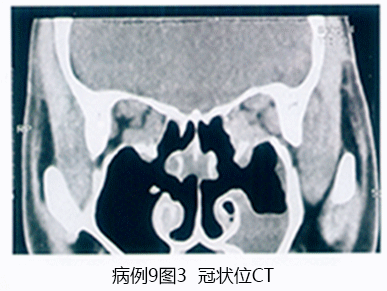

问题 1176

患者,男性, 28岁,主诉“双眼先后眼红、畏光、流泪、异物感9天, 左眼视力下降2天”。患者半月前曾至公共浴室洗浴,其后出现左眼红, 流泪,异物感等症状, 无明显分泌物,2天后右眼亦出现同样症状, 去医院就诊为“急性结膜炎”,予以局部抗病毒、抗生素滴眼液治疗, 但病情进一步发展,而且左眼出现视力下降, 遂至我院就诊。